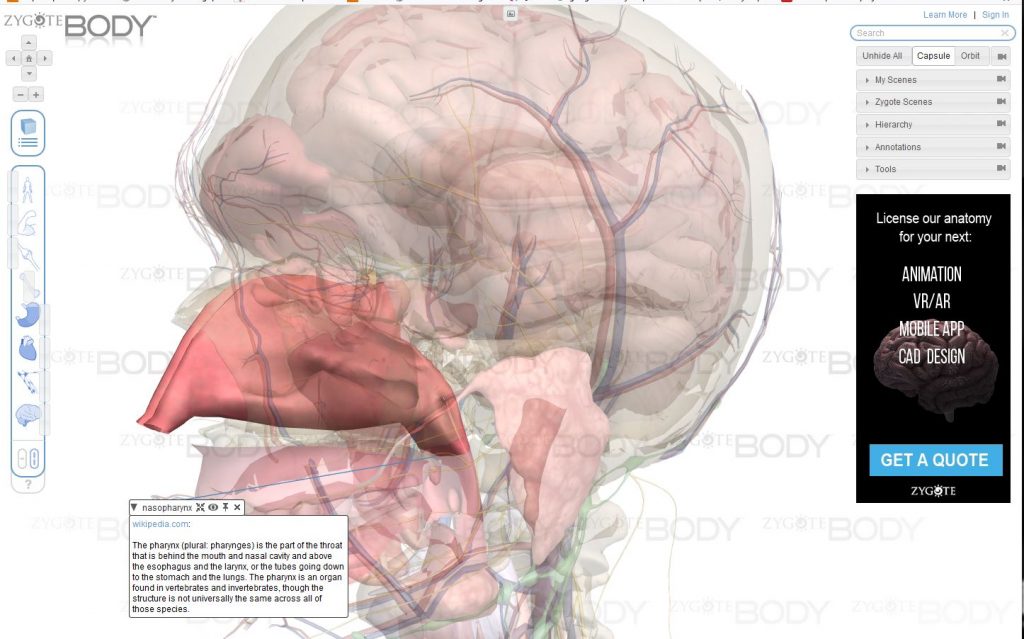

4/ On peut cliquer sur chaque élément pour avoir son nom et éventuellement une explication (en anglais):